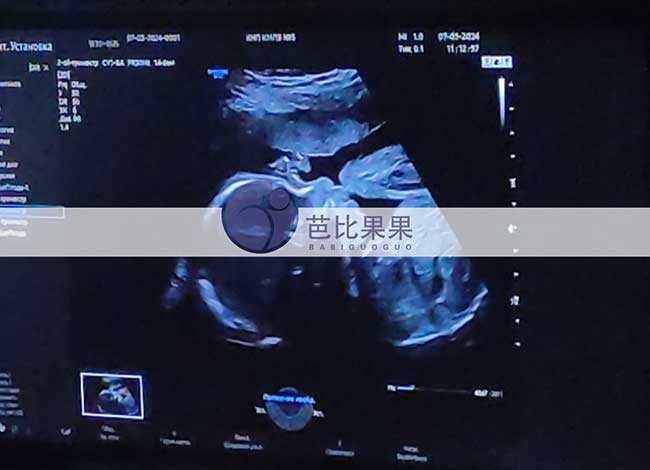

L女士家一如既往美丽的乌克兰试管妈妈来做四维检查

L女士家的乌克兰试管妈妈来做四维检查,还是一如既往的美丽,胎宝宝发育一切正常,8月就要和爸爸妈妈见面啦